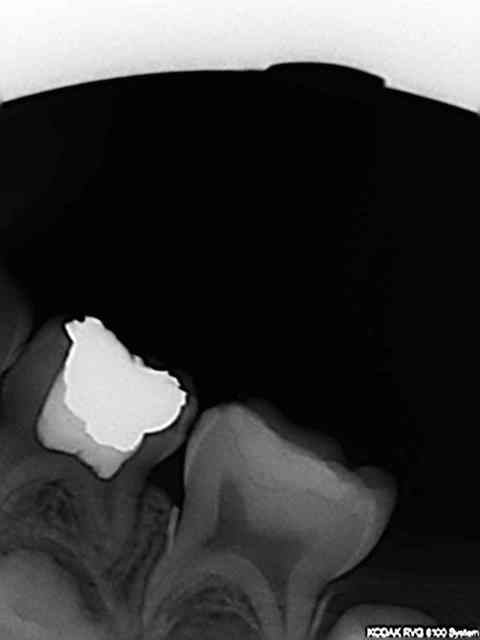

patiente 4 ans et 4 mois, super cool pulpo amg 74,compo 75 et si si ....digue.

Le souci c'est que j'ai pété le biseau d'une aiguille quick sleeper (la verte) SANS rotation plantée dans la racine mésiale de 75. Je l'ai laissée en place car la patiente de 4 ans et demi très gentille au demeurant commencait à montrer des signes d'impatience. Et en plus je sèche sur la CAT vu que c'est une première.))))

elle semble plantée dans le ligament. ça va faire une épine irritative.

C'est le germe de la 34 que l'on voit sur la Rx aussi proche que ça?